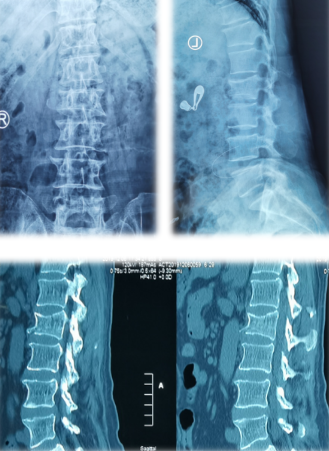

患者L2椎体骨质疏松性压缩性骨折

MRI

脊柱科孟磊副主任医师给老人仔细检查,老人L2椎体骨质疏松性压缩性骨折,需要进行PKP(经皮椎体后凸成形术)。